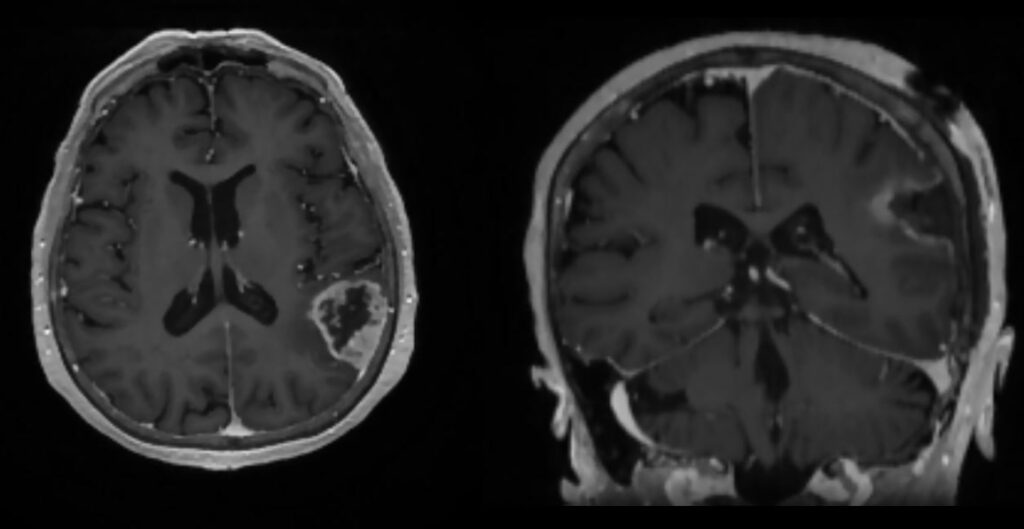

Пациентке выполнили обследования — в том числе МСКТ и МРТ головного мозга, показавшие объёмное образование в левой теменной доле. Опухоль и стала причиной состояния пациентки.

В феврале 2026 года пациентка была планово госпитализирована в Новосибирский НИИТО им. Я.Л. Цивьяна Минздрава России. Опухоль размером 3×4×5 см была тотально удалена под нейронавигационным контролем и направлена на дальнейшее гистологическое обследование, отмечает врач нейрохирургического отделения №1 Жорахан Назаров.

До и после операции